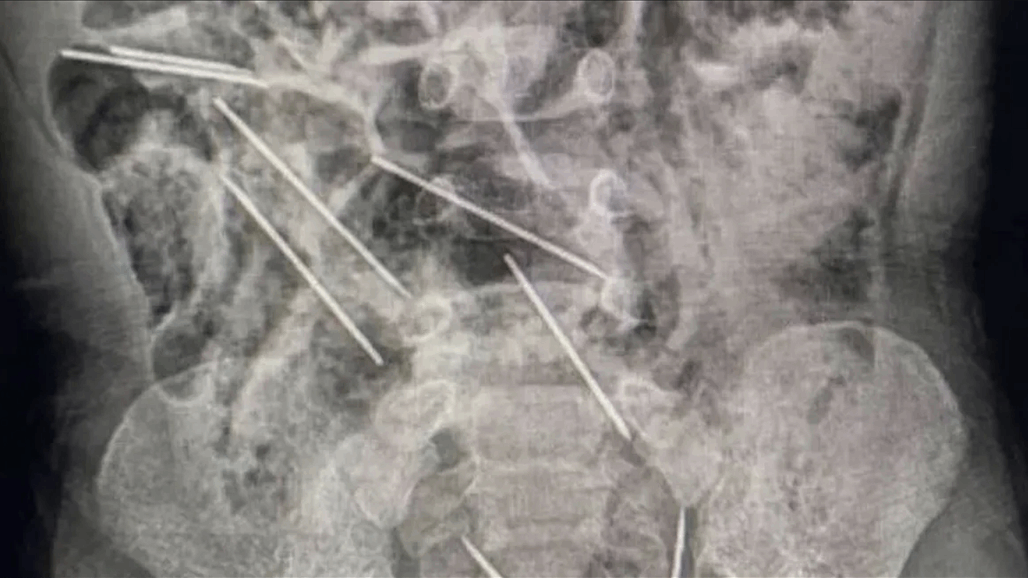

إنقاذ طفل ابتلع 8 إبر حقن في بيرو

أنقذ أطباء في شمال شرق

بيرو

حياة طفل عمره عامين بعد أن ابتلع ثماني إبر حقن وهو يلعب.

وقال الطبيب

إفراين سالاسار

"عندما كنا في

غرفة العمليات

وفتحنا بطنه وجدنا تلك القطع المعدنية، وأدركنا أنها كانت في الحقيقة إبرا".

وذكرت وسائل إعلام محلية أن الإبر كانت من تلك التي تستخدم لتطعيم حيوانات بمزرعة تعمل فيها والدة الطفل.

يعيش الطفل، الذي لم يتم الكشف عن اسمه، في منطقة تاراتوبو الزراعية على بعد حوالي 622 كيلومترا من العاصمة ليما.

وقالت والدته "ربما ابتلعها عندما كان يلعب هناك".

وذكرت وسائل الإعلام المحلية أن حياته ليست في خطر بعد الجراحة.